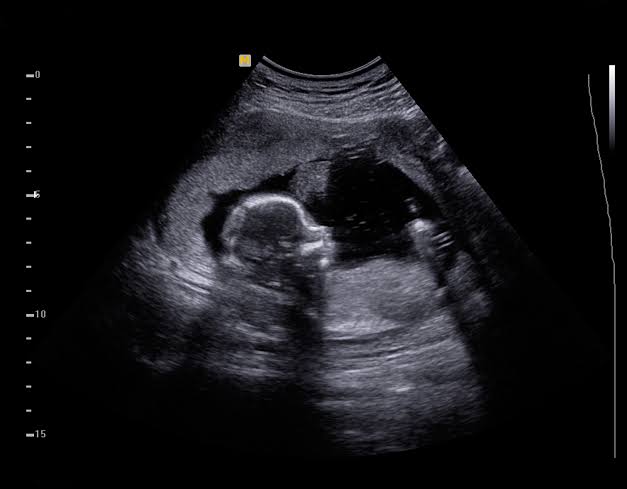

السونار لمعرفة نوع الجنين

الكثير يتساءل متى يبان نوع الجنين اذا كان ولد ؟ في الواقع يتم اللجوء إلى جهاز السونار من أجل معرفة نوع الجنين، حيث إنه يمكنه الكشف عن جنس الجنين بدرجة عالية من الدقة، وذلك بالاعتماد على التصوير بالموجات فوق الصوتية، وفي العادة يتم ذلك من بعد الشهر الرابع وبداية الخامس.

وبالرغم من أن الأعضاء التناسلية الخاصة بالجنين تبدأ بالتطور خلال الأسبوع السادس من الحمل، إلا أنه خلال الثلث الأول من الحمل تظهر الأجنة الذكور والإناث بشكل متشابه، ولكن حينما يحل الأسبوع الثامن عشر من الحمل يتمكن الطبيب من الكشف عن جنس الجنين.

ومن الجدير بالذكر فإن التصوير بالموجات فوق الصوتية هو أحد أبرز الاختبارات الشخصية التي لا تتضمن وجود أي مخاطر على السيدة الحامل أو الجنين نظرًا لأنه غير جائر، ويمكن للطبيب أن ينصح الأم بأن تخضع لهذا الفحص من أجل محاولة تشخيص بعض الأمراض التي قد يصاب بها الجنين مثل المشاكل بالقلب.